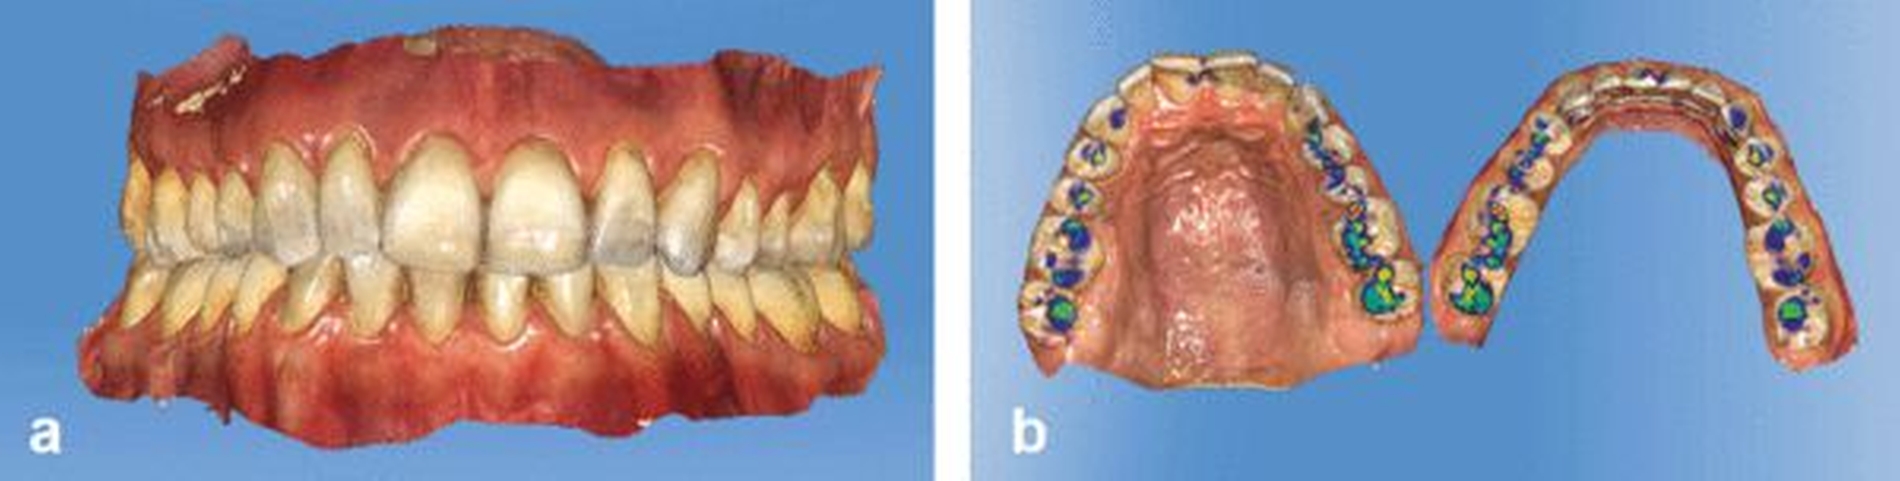

Während die ersten intraoralen Scanner noch umständlich in der Handhabung waren und beispielsweise vor dem Scan spezielle Puder in den Patientenmund eingebracht werden mussten, erreichen Kamera-basierte und Puder-freie Systeme mittlerweile Auflösungen von etwa 40 µm [Sun et al., 2018]. Sogar die ursprünglich empfohlenen Scanpfade können bei neueren Geräten in der Regel vernachlässigt werden [Medina-Sotomayor et al., 2018]. Bei vielen Programmen können zudem Kontaktpunkte direkt nach dem Bissregistrat virtuell angezeigt werden (Abbildung 1).